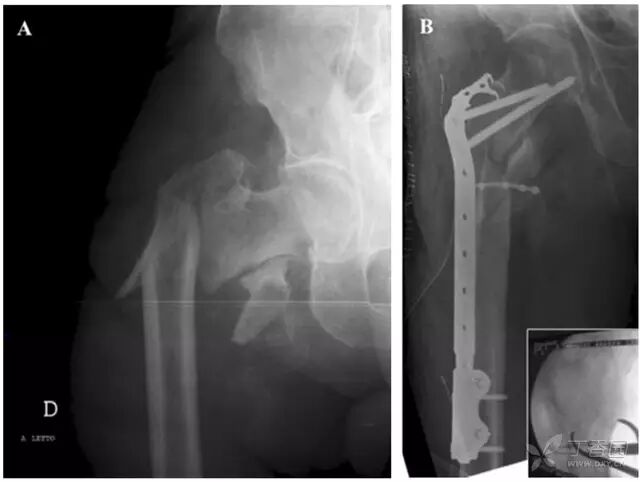

图 1 一名 87 岁男性患股骨近端骨折(AO31-A3 型)。A 前后位 X 线片示骨折增宽移位; B 术后患者股骨近端前后位 X 线片,采用干骺端动力钢板结合有限接触式钢丝联合固定,在钢板固定之前先复位骨折端并用钢丝固定小转子